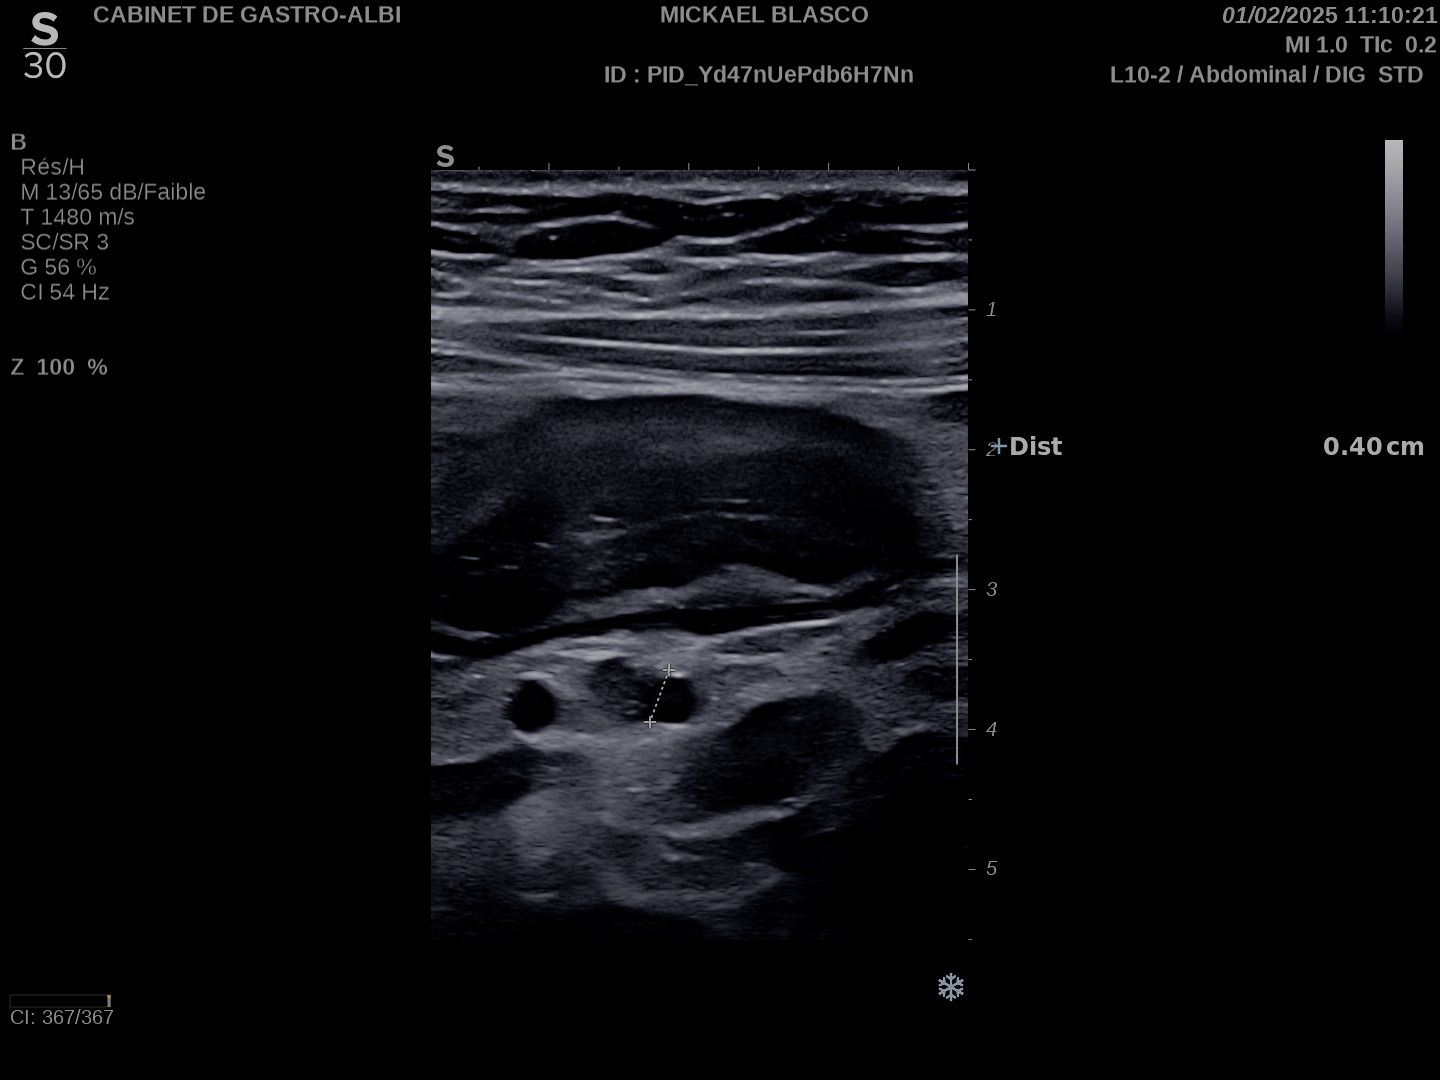

Epaississement considérable par endroit (10 ou 11 mm), disparition totale de la structure en couches, déformation de la surface avec ulcérations, déformation des contours, infiltration de la graisse, hyperactivité Doppler

Le Score de Milan (MUC) est à 17.4

Les images échographiques correspondent parfaitement aux images endoscopiques, et sont finalement beaucoup plus précises que les images scanographiques.